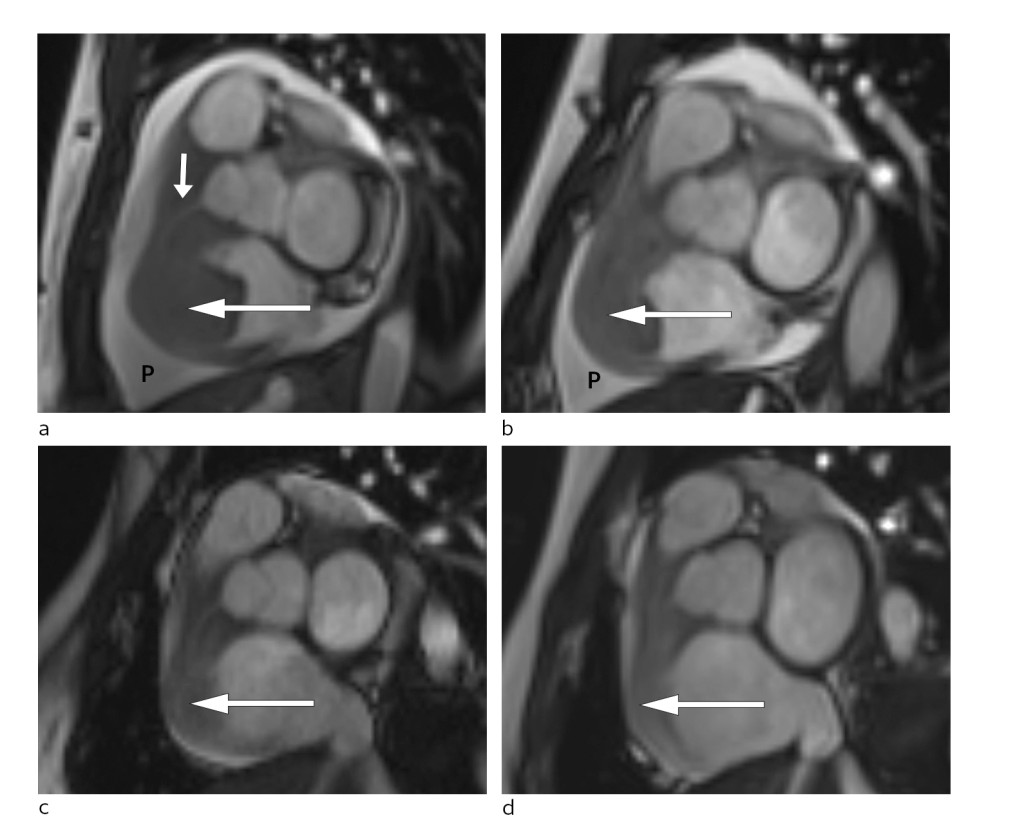

Only hours after treatment, the patient noticed decreasing chest pain and reduced dyspnoea. Two days later, it was possible to perform cardiac MRI. This confirmed persistent tumours in the right atrium and right ventricle with growth through the ventricular wall and fusion of the tricuspid leaflet (Fig. 3).

Figure 3 Short axis view of cardiac MRI at different disease stages. a) Large tumour at the time of diagnosis (large arrow)…

Figure 3 Short axis view of cardiac MRI at different disease stages. a) Large tumour at the time of diagnosis (large arrow) in the right side of the heart and significant pericardial effusion (P). The right coronary artery (small arrow) passes through the tumour. Follow-up MRI showing gradual reduction of tumour size (arrow) and pericardial effusion (P) at b) one week post-diagnosis, c) eight weeks post-diagnosis and d) 20 weeks post-diagnosis.

During this period, the patient was monitored in the cardiac observation unit. No arrhythmias or other complications of treatment were observed. She received low dose fractionated heparin as thrombosis prophylaxis. Repeated MRI scans, performed three days after initiation of the CHOP regimen, showed significant regression of the mass in the right side of the heart and almost total regression of the intracavitary components. The right atrioventricular opening was significantly larger than in the initial MRI scan (Fig. 3).

The patient underwent a further treatment cycle. Radiological assessment after the second treatment showed almost total regression of the abdominal tumour (Fig. 3). We have continued with the R-CHOP regimen, which has kept the disease in remission ever since.

Corticosteroid therapy was started before the final histology results were available. Corticosteroids have a general anti-inflammatory effect, in addition to a direct cytotoxic effect on lymphoid cells. Once the histology results were available, it was possible to begin a more targeted treatment of the cancer. It was important in this case to monitor the treatment response of both the primary abdominal tumour and the cardiac mass because a causal relationship between them had not been definitively established. The observed response (Fig. 3) was consistent with such a relationship.